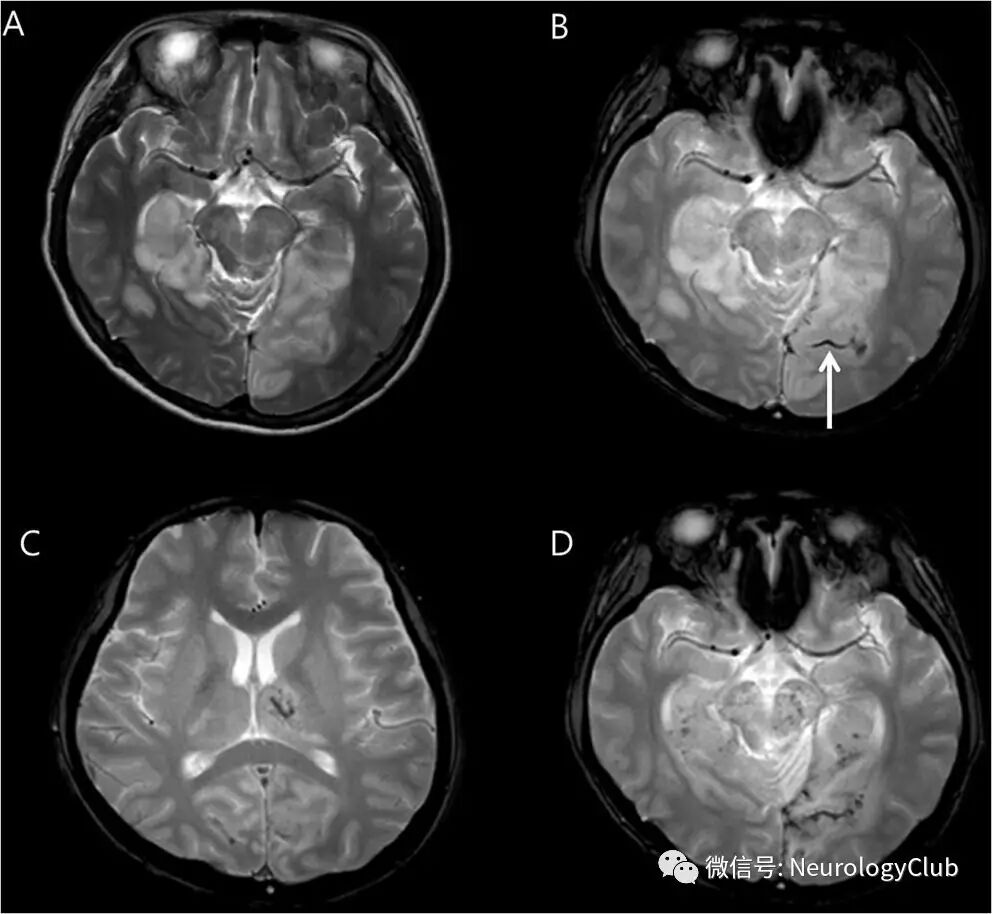

行DWI检查可见双侧丘脑,枕叶和左侧脑桥中央病灶(图1A-D)。考虑为急性缺血性卒中,尽管头颅CTA证实后循环无明显狭窄或闭塞。予阿替普酶0.9mg/kg治疗,但患者症状未见改善。

1天后复查DWI,见病灶延伸累及双侧丘脑后部,中脑,脑桥和小脑(图1E-H)。T2WI可见颞枕叶血管源性水肿,梯度回波序列上左侧丘脑,左侧枕叶,中脑,脑桥和左侧小脑(图2A-B)点状出血。此外,梯度回波序列还可见沿着左侧枕叶脑沟的晕状伪影(blooming artifact),符合皮层静脉血栓形成(图2B,箭)。MRA同样未见颅内动脉狭窄或闭塞(图3A)。后一天再复查梯度回波序列可见点状出血进展,MRV上直窦管腔不规整(图3B,箭)。

(图1:A-D:起病初DWI;E-H:复查DWI)